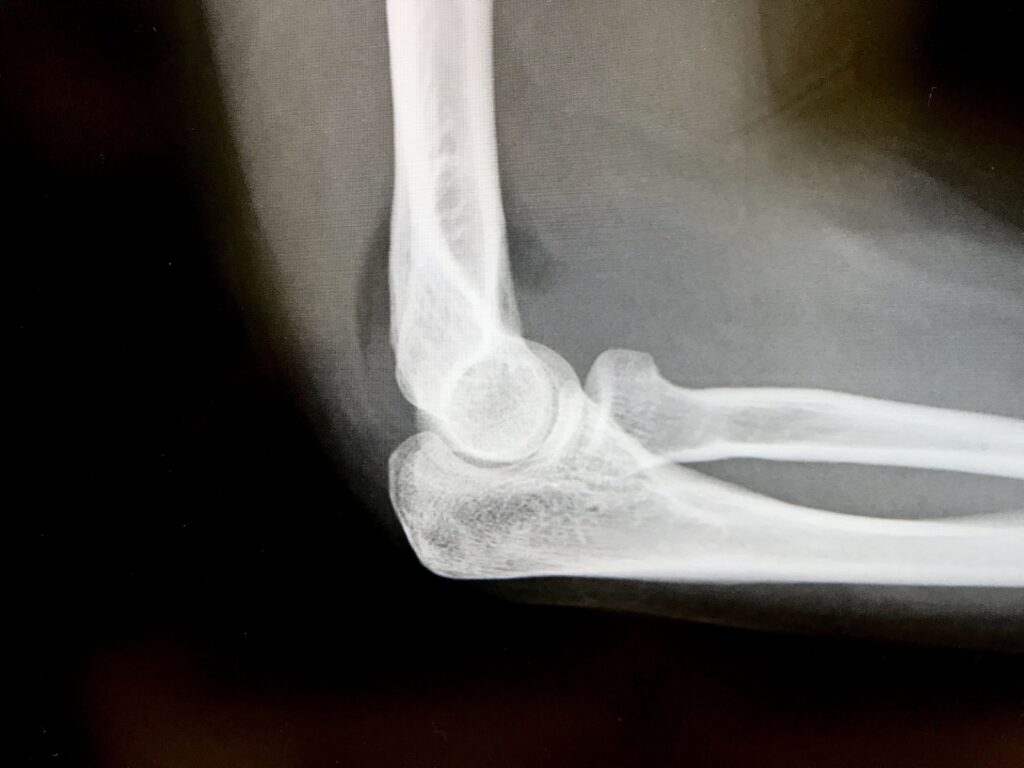

1. レントゲン検査

レントゲン検査

必要に応じてレントゲン検査を行い、骨の状態などを確認し、症状との関係を確認します。